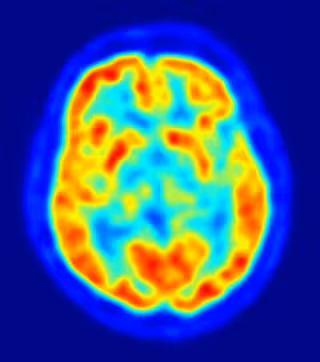

La depresión y los problemas del sueño comparten una conectividad funcional entre las áreas del cerebro asociadas con la memoria a corto plazo, según un estudio realizado por investigadores de la Universidad de Warwick (Reino Unido) y la Universidad de Fudan (China) y que ha sido publicado en la revista 'JAMA Psychiatry'.

Analizando datos de alrededor de 10.000 personas, los investigadores examinaron los mecanismos neuronales subyacentes a la relación entre la depresión y la calidad del sueño. Así, en los cerebros de aquellos que padecen problemas depresivos, descubrieron una fuerte conexión entre la corteza prefrontal dorsolateral (asociada con la memoria a corto plazo), el precúneo (asociado con el 'yo') y la corteza orbitofrontal lateral (asociada con la emoción negativa).

En concreto, el análisis mostró que estas conectividades funcionales subyacen a la relación entre los problemas depresivos y la calidad del sueño. "El aumento de la conectividad funcional entre estas regiones del cerebro proporciona una base neural de cómo la depresión se relaciona con la mala calidad del sueño", han aseverado los expertos.

Y es que, prosigue, sus resultados son consistentes con áreas del cerebro involucradas en la memoria a corto plazo (corteza prefrontal dorsolateral), el yo (precúneo) y la emoción negativa (la corteza orbitofrontal lateral) que están altamente conectadas en la depresión, lo que provoca un aumento de los pensamientos de rumia que son, al menos, parte del mecanismo que afecta a la calidad del sueño.

"La relación entre la depresión y el sueño se ha observado durante más de cien años, y ahora hemos identificado por primera vez los mecanismos neuronales de cómo están conectado. Estos hallazgos proporcionan una base neuronal para comprender cómo la depresión se relaciona con la mala calidad del sueño y esto, a su vez, tiene implicaciones para el tratamiento de la depresión y la mejora de la calidad del sueño debido a las áreas cerebrales identificadas", han zanjado los expertos.